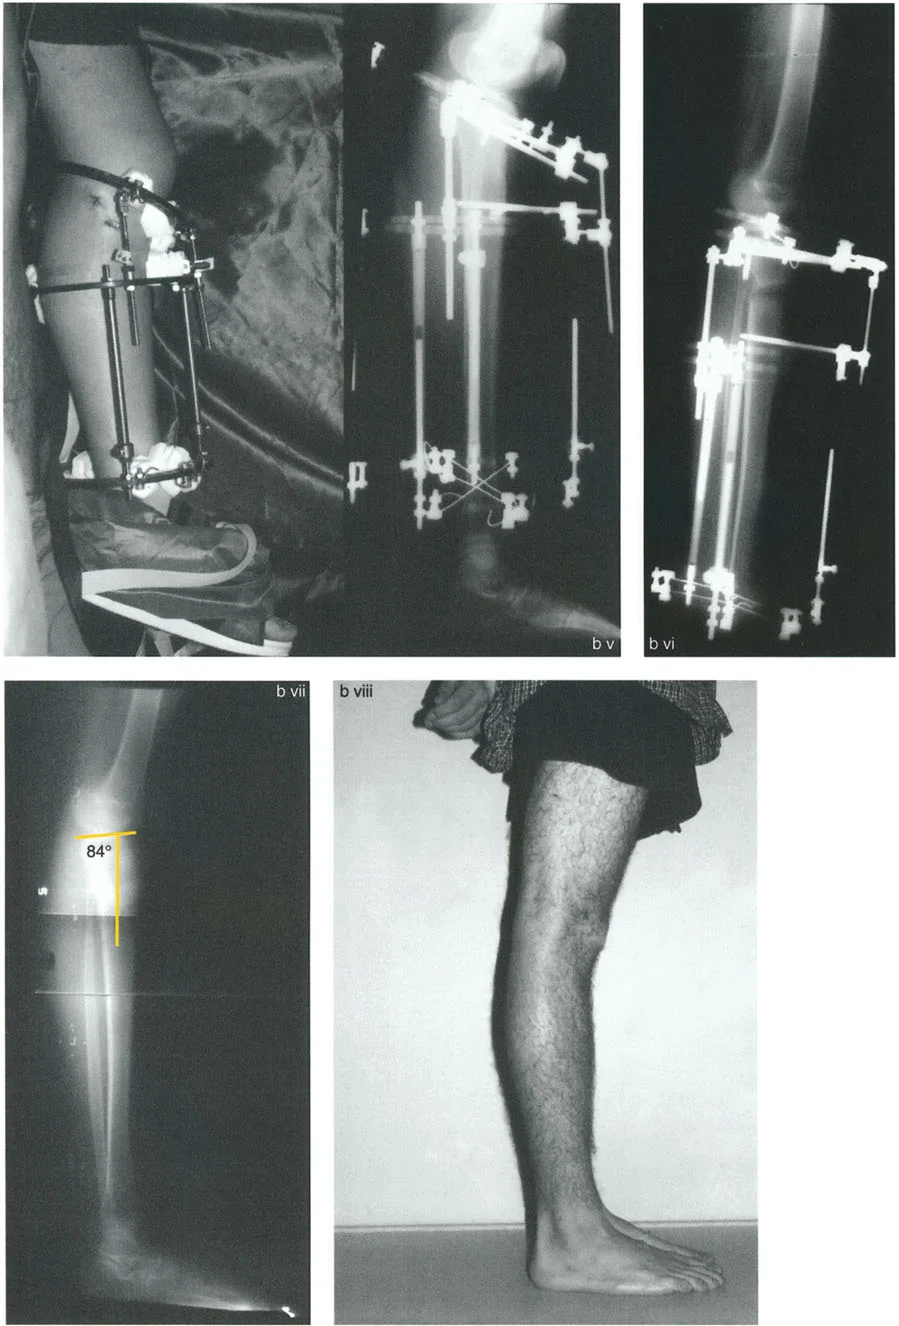

الارتداد الظنبوبي (Tibial Recurvatum):

- ينتج عن انحناء مفرط في الجزء العلوي من عظم الساق (الظنبوب)، مما يدفع الركبة إلى التمدد الزائد.

- يمكن أن يحدث بسبب توقف نمو جزئي في عظم الساق القريب، كما هو الحال في بعض حالات الكسور أو العدوى التي تؤثر على صفيحة النمو.

- حالة مريضة تبلغ من العمر 24 عامًا عانت من كسر في الفخذ في سن 12 عامًا، وعولجت بالشد. تسبب دبوس الشد في توقف نمو جزئي في الجزء القريب من عظم الساق، مما أدى إلى ارتداد ظنبوبي.

- تقييم مدى الحركة: يتم قياس مدى حركة الركبة، بما في ذلك أقصى تمدد وأقصى انثناء. يتم تحديد درجة فرط التمدد (HE - Hyperextension) أو درجة تقلص الانثناء الثابت (FFD - Fixed Flexion Deformity).

تُعد الأشعة السينية ضرورية لتقييم التشوهات العظمية في المستوى السهمي. يتم التقاط صور شعاعية جانبية (Lateral X-rays) للركبة في وضعيات مختلفة (تمدد كامل، انثناء).

- زاوية الانحناء البعيدة للفخذ (PDFA - Posterior Distal Femoral Angle): تقيس زاوية الجزء السفلي من عظم الفخذ. القيمة الطبيعية حوالي 84 درجة. الزيادة في هذه الزاوية (أكثر من 84 درجة) تشير إلى ارتداد فخذي.

- زاوية الانحناء القريبة للظنبوب (PPTA - Proximal Posterior Tibial Angle): تقيس زاوية الجزء العلوي من عظم الساق. القيمة الطبيعية حوالي 80 درجة. الزيادة في هذه الزاوية (أكثر من 80 درجة) تشير إلى ارتداد ظنبوبي.

2. العلاج الجراحي: قطع العظم (Osteotomy)

الهدف من جراحة قطع العظم هو إعادة محاذاة العظام وتصحيح التشوه الزاوي في المستوى السهمي، لاستعادة وظيفة الركبة الطبيعية واستقرارها.

أ. قطع العظم الفخذي لتصحيح الارتداد الفخذي:

- متى يتم إجراؤها: عندما يكون التشوه الرئيسي في عظم الفخذ البعيد.

- الإجراء: يتم إجراء قطع للعظم (عادة قطع عظم انثناء) في الجزء البعيد من عظم الفخذ، عند مركز دوران الزاوية (CORA)، لإعادة محاذاة العظم.

- الهدف: تصحيح فرط تمدد الركبة واستعادة المحاذاة الطبيعية.

- مثال: لتصحيح ارتداد فخذي بمقدار 20 درجة، يتم إجراء قطع عظم انثناء فخذي بمقدار 20 درجة.